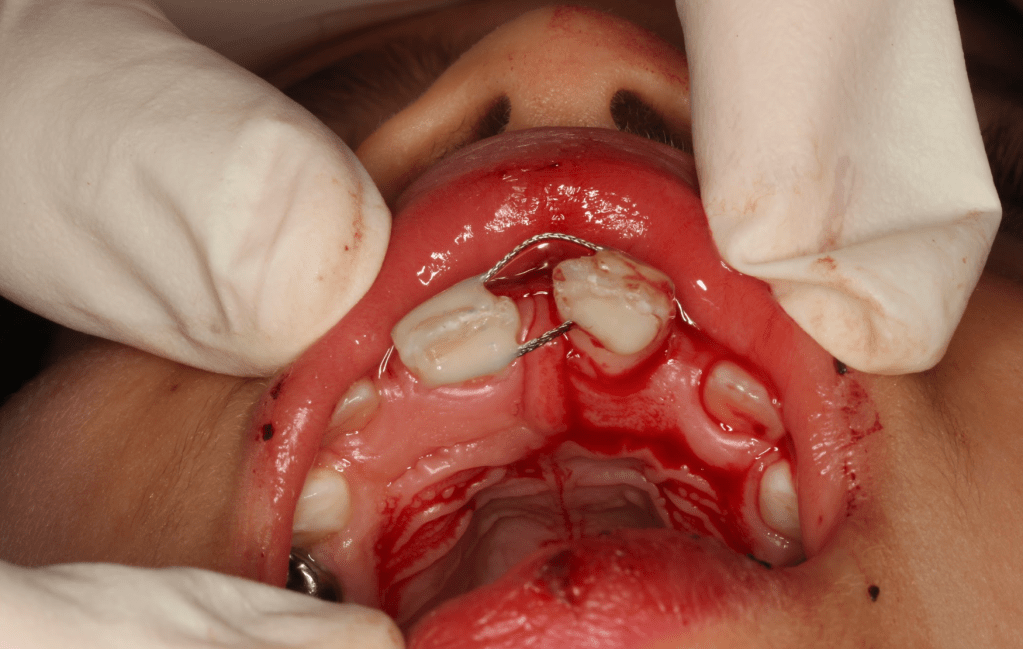

Gingivectomía + pulpotomía biodentine + reconstrucción

Reconstrucción preendodóntica

Reco pre-endo gingivectomái, pared yuxtaosea

Reco preendo + gingivectomía